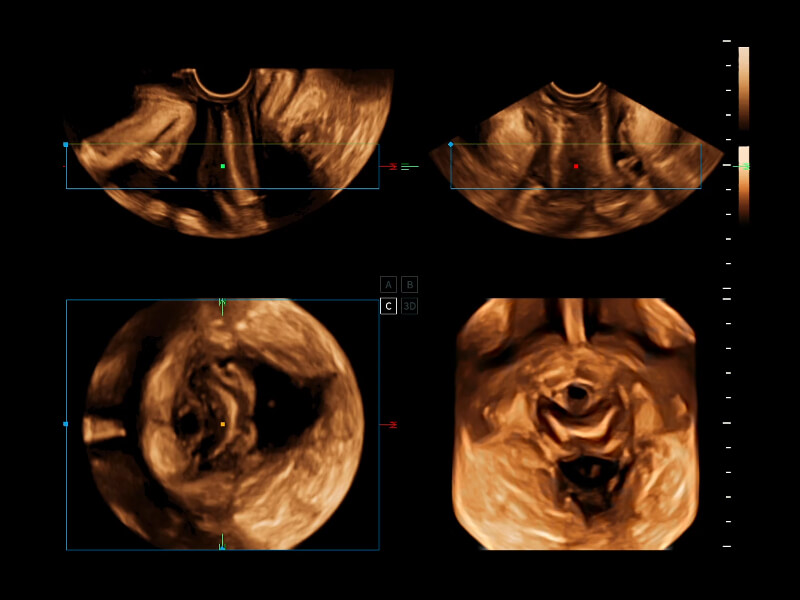

女性健康綜合解決方案

夢(mèng)溪?P80以“關(guān)愛女性”為基石,提供全方位的解決方案,量身定制以滿足女性的健康需求,涵蓋婦科、生殖健康檢查、產(chǎn)前篩查及產(chǎn)后康復(fù)等領(lǐng)域。

生殖健康 早孕篩查 中晚孕檢查 胎心篩查 盆底檢查 婦科關(guān)愛

時(shí)間空間相關(guān)成像